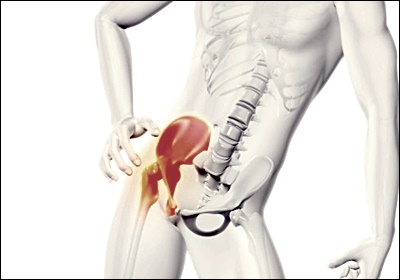

고관절 통증의 증상은 다양하게 나타날 수 있습니다. 가장 흔한 증상은 고관절 부위의 둔통입니다. 이 통증은 서서히 시작되어 점차 심해지는 경향이 있으며, 활동 시 악화되고 휴식 시 완화되는 특징이 있습니다. 또한 고관절 통증은 종종 허벅지 앞쪽이나 무릎까지 퍼질 수 있습니다. 일부 환자들은 걸을 때 절뚝거림을 경험하거나, 장시간 앉았다 일어날 때 뻣뻣함을 느낍니다. 심한 경우에는 관절의 가동 범위가 제한되어 일상생활에 지장을 줄 수 있습니다. 밤에 통증이 심해져 수면을 방해하는 경우도 있습니다.

고관절 통증은 많은 사람들이 겪는 불편한 증상 중 하나입니다. 일상생활에 지장을 주는 이 통증의 원인과 증상, 그리고 효과적인 치료법에 대해 알아보겠습니다. 고관절은 우리 몸의 중요한 관절 중 하나로, 이 부위의 통증은 삶의 질을 크게 저하시킬 수 있습니다. 이 글을 통해 고관절 통증에 대한 이해를 높이고, 적절한 대처 방법을 찾는 데 도움이 되길 바랍니다.